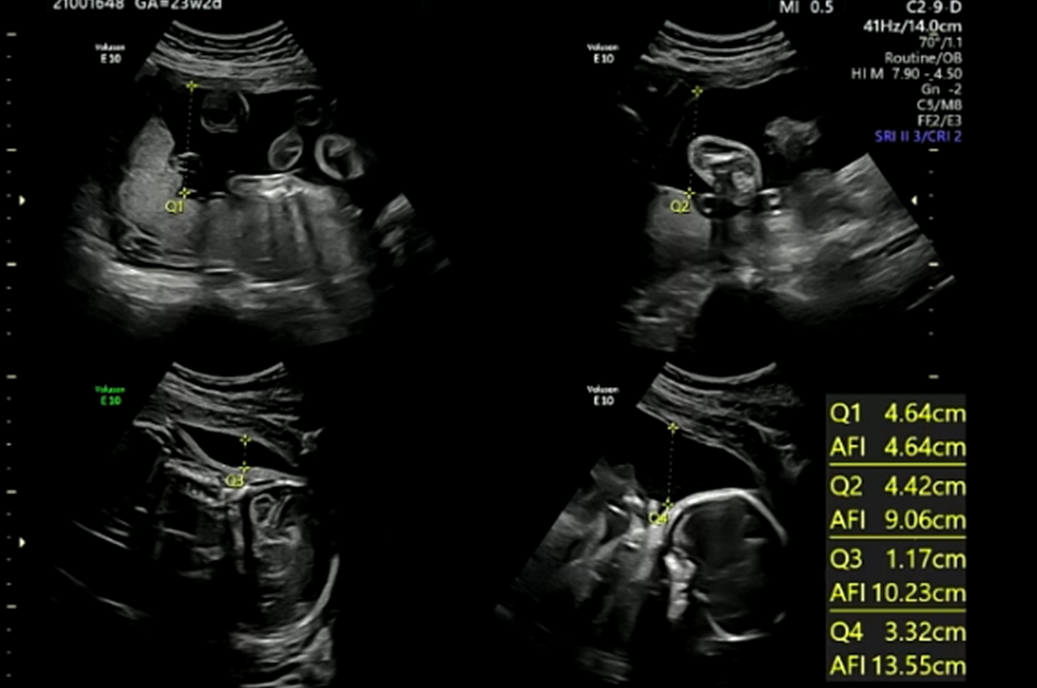

태반(양수)

※ 초음파 용어) AFI : 양수지수

양수지수도 문제있는 지 확인하였는데 다행히 별 문제 없었다.